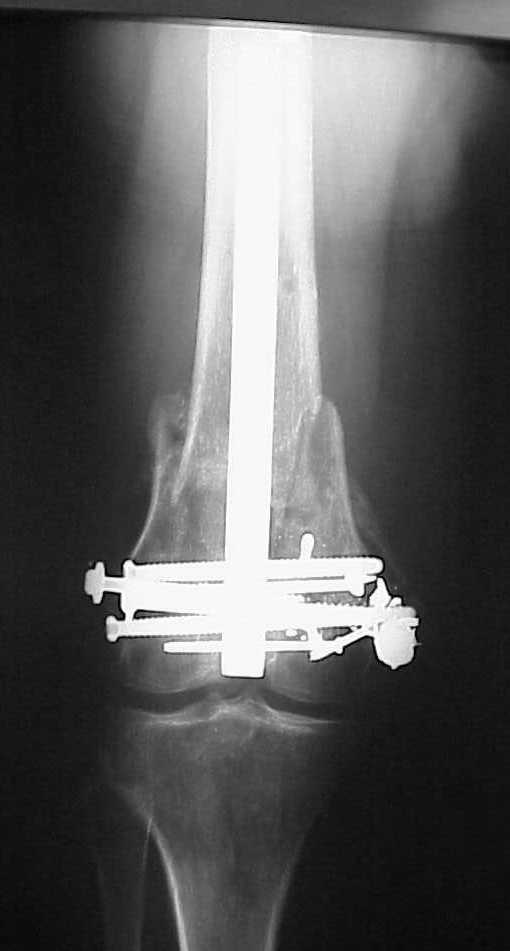

> How the screws should be placed?

Use 6.5 mm cannulated screws if you have and

place one anterior to where IMN will go if anterior cortex if insufficient and AP screws on either side of the IMN out of the trochlea to provide some additional varus/valgus stability. I worry about the leg going into valgus w/the lack of lateral cortex.

See attached case that was done several years ago before LISS. He had comminuted trochlea and anterior blocking screws were used to prevent anterior IMN cut-out.